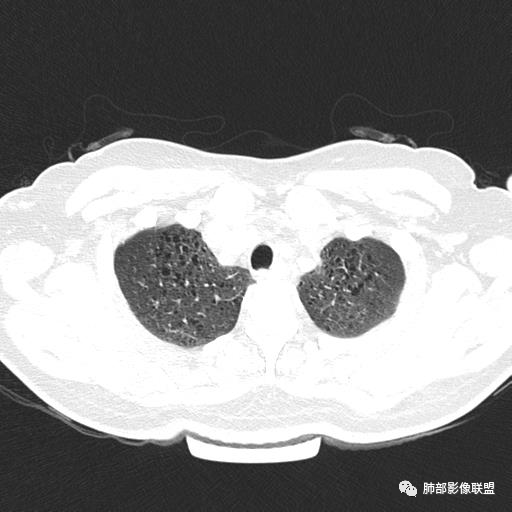

女,46,活动性气喘1年。苯吸入史半年。胸部CT:两肺弥漫囊腔,上至肺尖,下至肋膈角,形态类似小囊腔。考虑:LAM,鉴别LIP,BHD,PLCH等。

双肺弥漫大小不一薄壁含气囊腔,囊间肺组织正常,正常肺背景,肺尖肺底受累;青年女性,气喘,支持LAM

CT表现:双肺弥漫大小不等的薄壁囊腔,囊壁<2mm,外形规则,血管影多位于囊腔周围,囊腔之间肺组织正常,随着疾病进展到晚期,囊腔变大、增多,不可胜数,囊腔可融合成较大的囊,与肺气肿相似,形成间质性肺纤维化。部分病例可出现结节影。